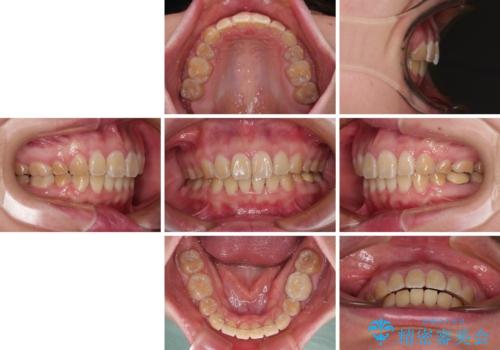

抜歯矯正で唇を閉じやすく ワイヤー矯正

- 口元の閉じにくさと、前歯のでこぼこの歯並びを気にして来院された患者様です。

口元を積極的に引っ込めるために、上下左右の小臼歯計4本を抜歯することとしました。

4本の歯を抜歯したことで、飛び出していた口元が引っ込み、横顔が大きく改善されました。